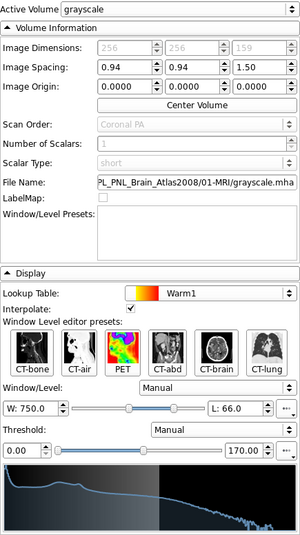

| qMRMLVolumeInfoWidget |

|

A widget that shows volume internal data properties |